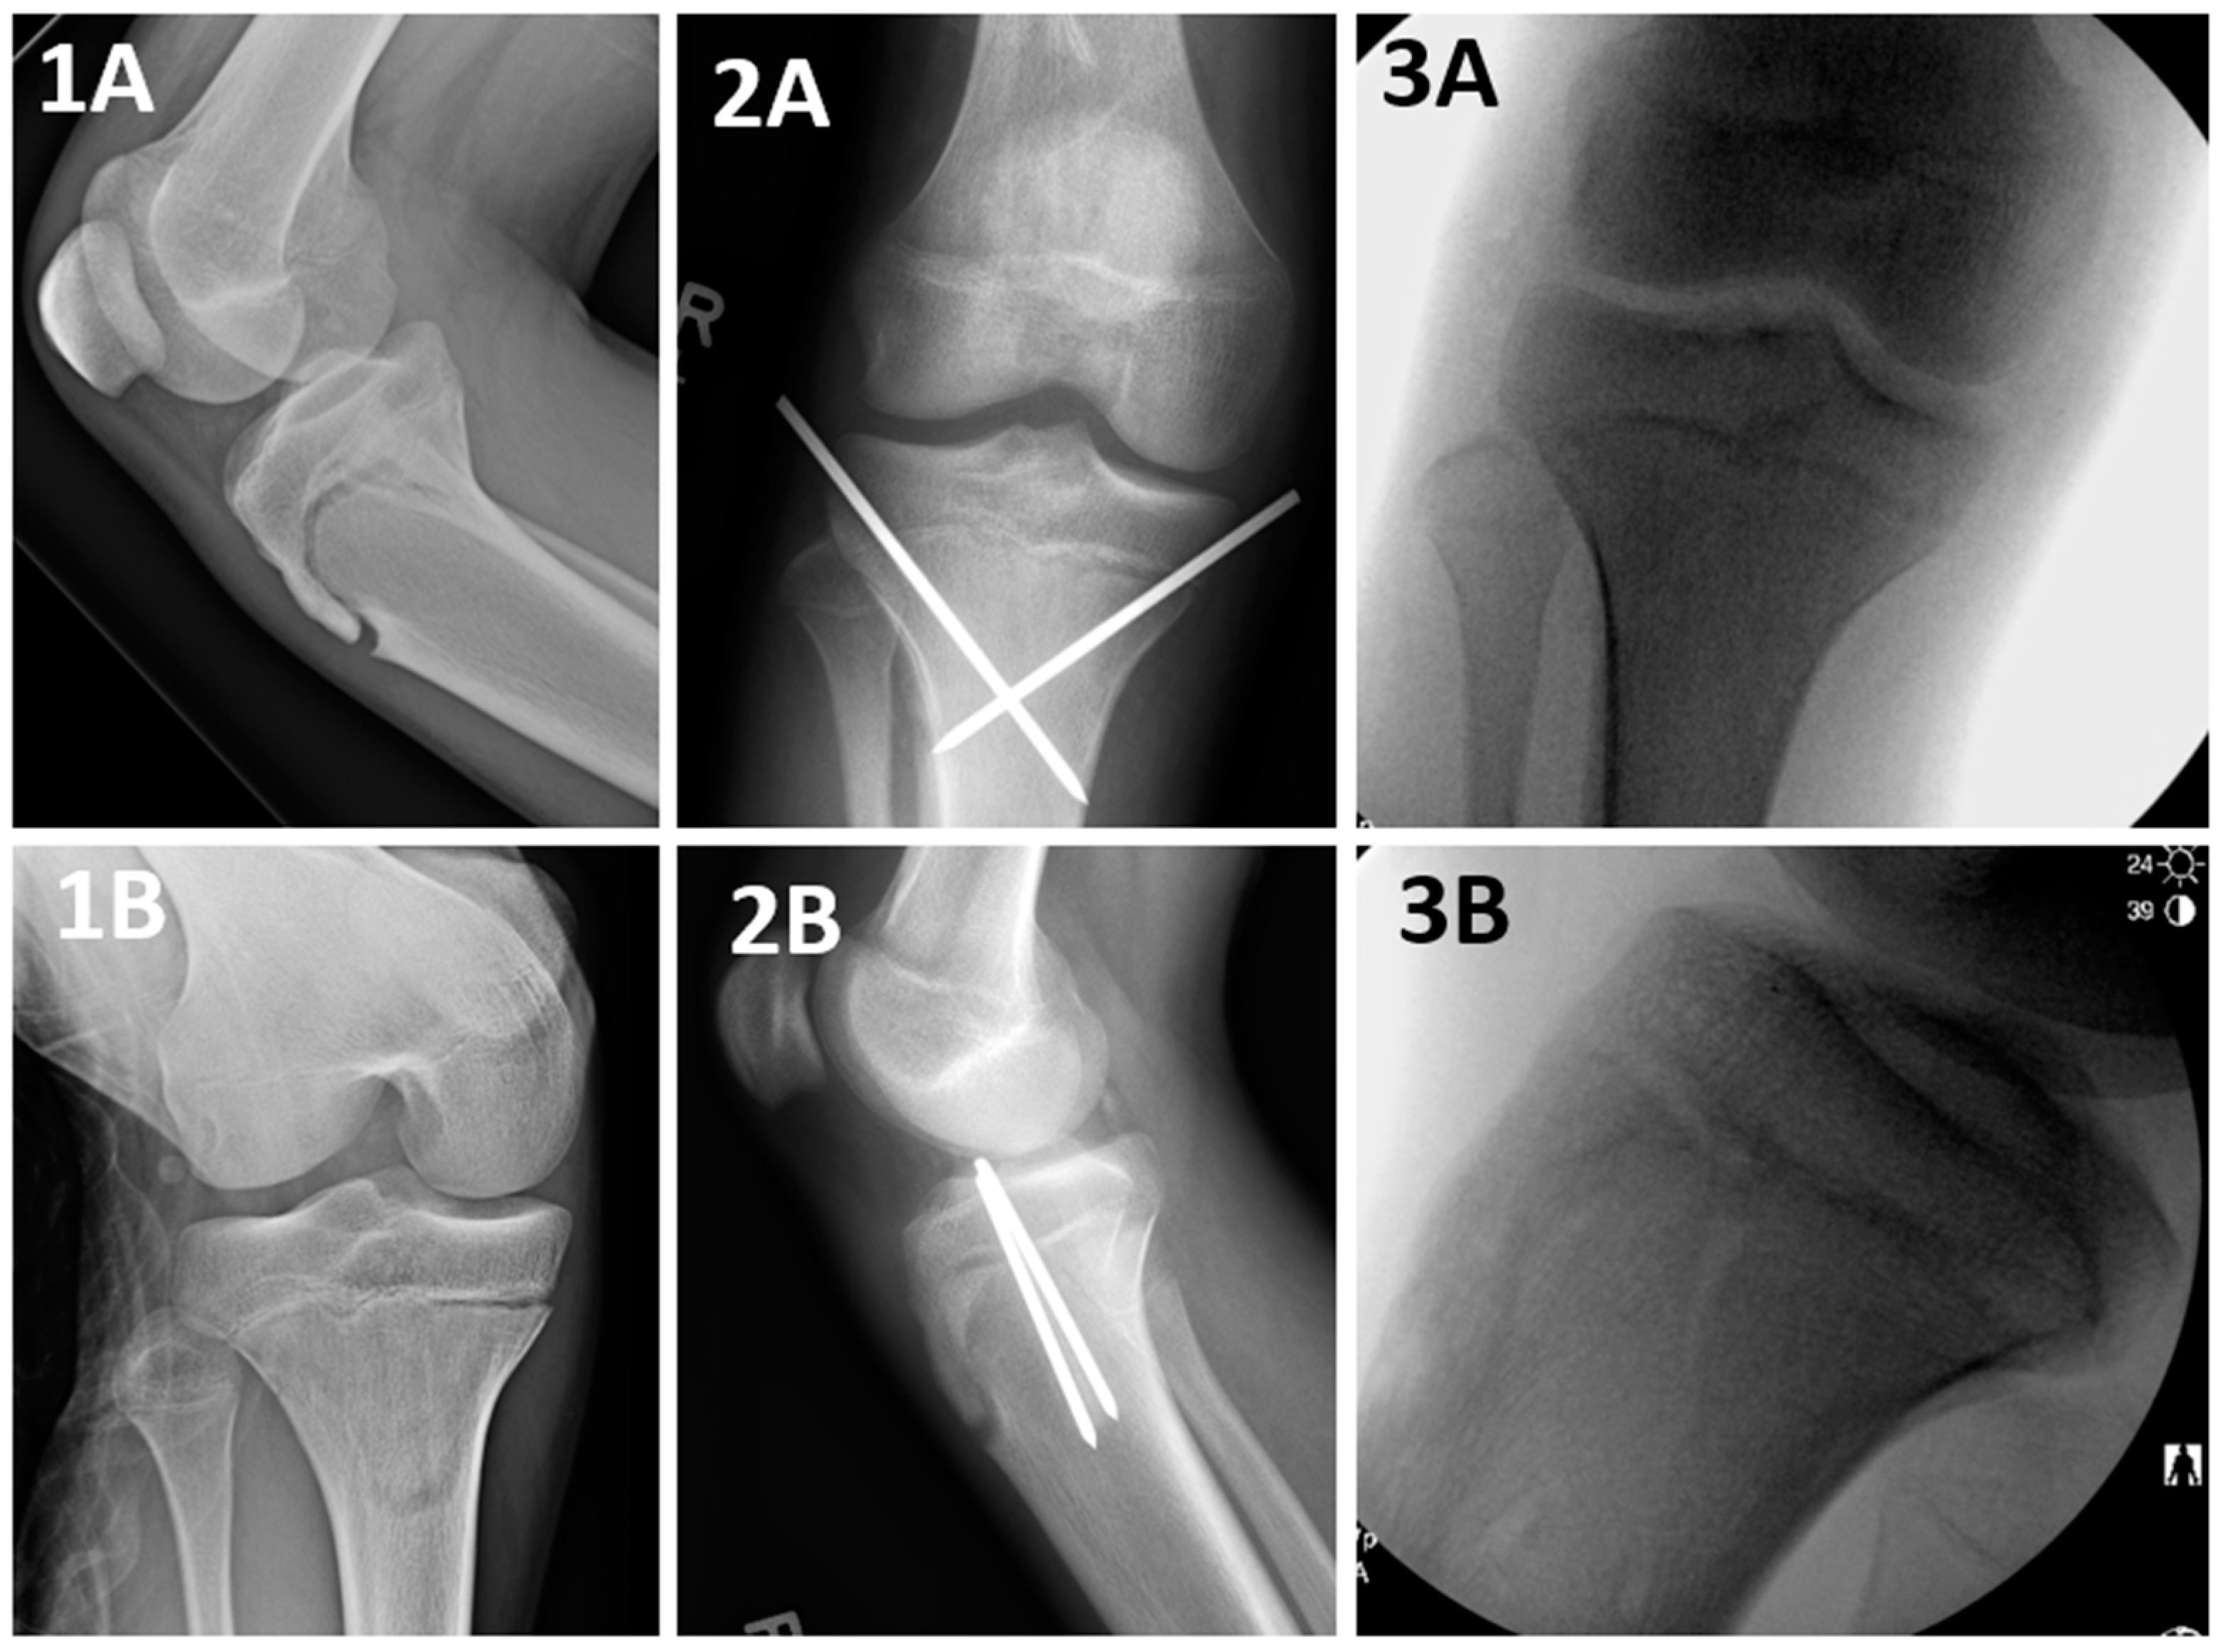

Loss of Fixation of a Type IV Supracondylar Humerus Fracture。Type 4 Tibial Tuberosity Avulsion Fractures: Surgical。Spinal Trauma Specific Injuries - OrthoPaedia。イタリア出身のデスメタル/エクストリームメタルバンドNERVEが2013年に発表した3rdアルバム『Fracture』輸入盤デジパックディスク無音部に少し傷がありますが再生には問題ありません。。